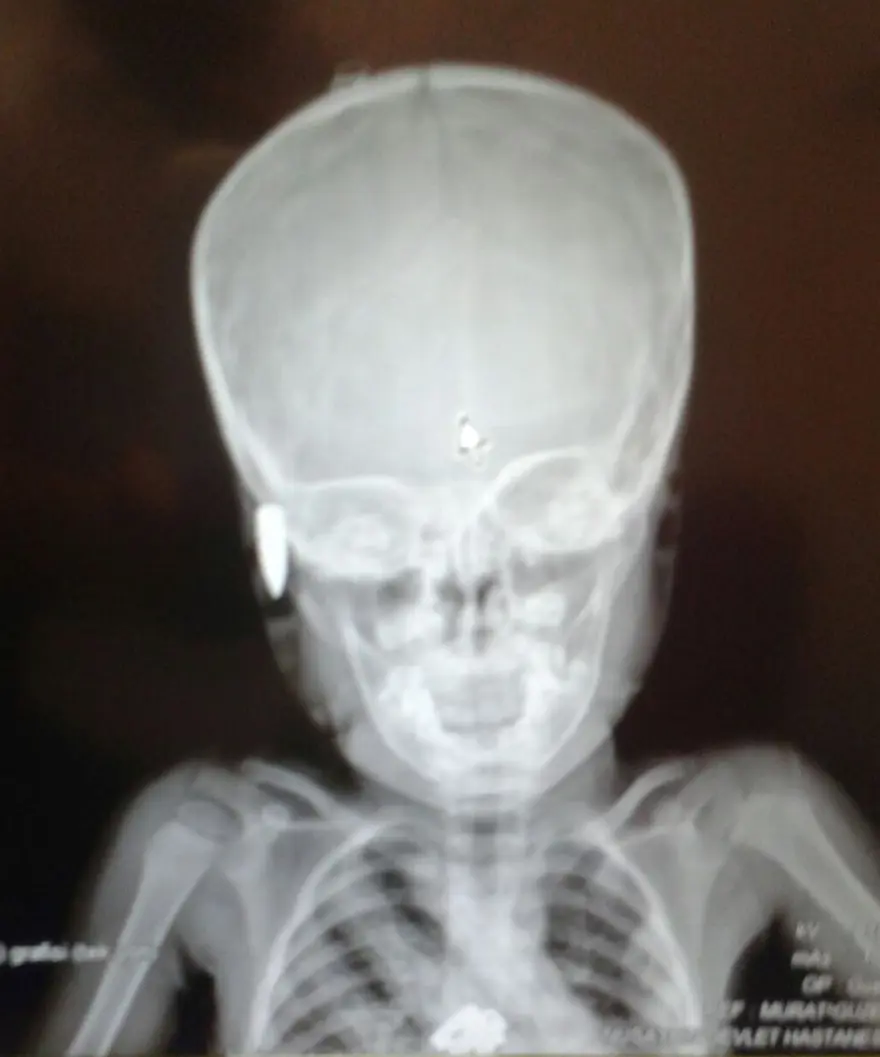

Mardin'in Nusaybin ilçesinde, evinin balkonunda oyun oynayan 3 yaşındaki bir çocuğun başına mermi isabet etti. Küçük çocuk, yoğun bakıma alındı.

Nusaybin'de Barış Mahallesi İnce Küme Sokak'taki evlerinin ikinci katındaki balkonunda oynayan İsa D.'nin başına, nereden atıldığı belli olmayan otomatik silaha ait mermi isabet etti.

Ailesi tarafından Nusaybin Devlet Hastanesi'ne kaldırılan küçük çocuk, burada yapılan ilk tedavisinden sonra önce Mardin, sonra da Şanlıurfa Devlet Hastanesi'ne sevk edildi.

Yoğun bakım servisinde tedavisi süren çocuğun durumunun ağır olduğu belirtildi.